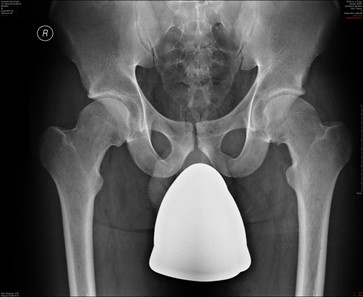

Typowymi objawami zespołu konfliktu udowo-panewkowego (FAI) typu CAM są:

1) nadmierne zakrycie głowy przez panewkę stawu biodrowego;

2) tylne odchylenie panewki stawu biodrowego;

3) obecność „objawu skrzyżowania” na przednio-tylnym RTG;

4) nadmierne kościotworzenie przy połączeniu głowy i szyjki;

5) w obrazie osiowym MRI ośrodek głowy kości udowej znajduje się z boku linii łączącej krawędzie panewki.

Prawidłowa odpowiedź to: